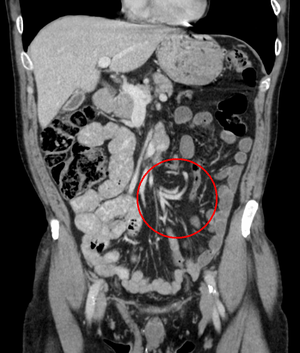

After taking a thorough history, the diagnosis of colonic volvulus is usually easily included in the differential diagnosis. Abdominal plain x-rays are commonly confirmatory for a volvulus, especially if a "bent inner tube" sign or a "coffee bean" sign are seen. These refer to the shape of the air filled closed loop of colon which forms the volvulus. Should the diagnosis be in doubt, a barium enema may be used to demonstrate a "bird's beak" at the point where the segment of proximal bowel and distal bowel rotate to form the volvulus. This area shows an acute and sharp tapering and looks like a bird's beak. If a perforation is suspected, barium should not be used due to its potentially lethal effects when distributed throughout the free infraperitoneal cavity. Gastrografin, which is safer, can be substituted for barium.

- Abdominal x-ray – tire-like shadow arising from right iliac fossa and passing to left